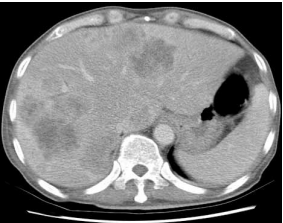

19 一位 73 歲男性病人因腹瀉 2 個月並體重減少 10 公斤而由門診住院。門診超音波檢查顯示有多個肝 腫瘤。大腸鏡檢查發現上行結腸有突起之腫瘤,病理檢查證實為腺癌。病人之 B 型肝炎、C 型肝炎 標記陰性,胎兒蛋白正常,但癌胚胎抗原(CEA)為 1160 ng/mL。病人腹部電腦斷層如附圖。下列 何者為此病人之最適合之 Dukes 分期? (A) B (B) C (C) D (D) E